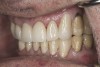

(23.) Provisionals, right lateral, closed view.

Figure 23

(24.) Provisionals, anterior, closed view.

Figure 24

(25.) Provisionals, left lateral, closed view.

Figure 25

(26.) Provisionals, right anterior, close-up view.

Figure 26

(27.) Provisionals, anterior, close-up view.

Figure 27

(28.) Provisionals, left anterior, close-up view.

Figure 28